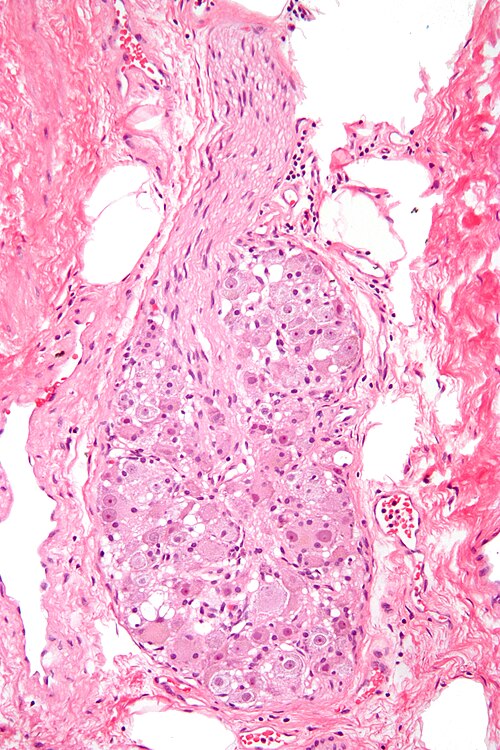

Nephron · CC BY-SA 3.0 · source